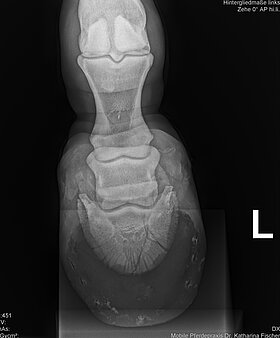

Röntgen-Equipment

Mit akkubetriebenen Röntgengeräten können wir bei orthopädischen Untersuchungen oder Verletzungen (auch auf der Koppel oder an einem Offenstall) ohne Strom direkt vor Ort röntgen und die Bilder gleich auswerten.